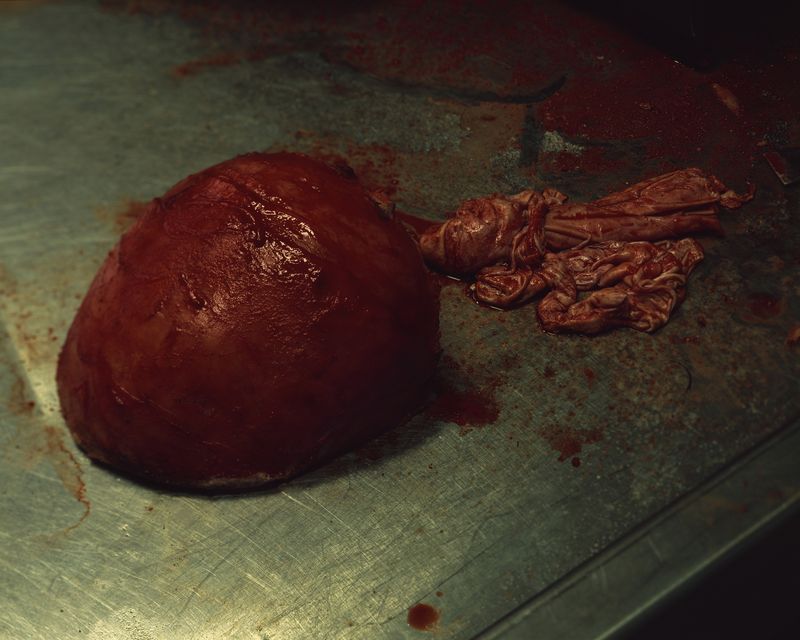

My work asks questions and challenges contemporary social and cultural attitudes towards the perception of death, the quality of life, reflections on the essence of humanity on philosophical and technological grounds. The story of our corporeality aims to begin a discourse about what has been tabooed or is socially marginalized:

medical bioengineering, technology in medical service, change in the perception of a dead body and the aspect of loss. Such a discourse could reveal the needs and solutions for the development of bioengineering in Poland. The increasingly appearing idea of transhumanism in this aspect considers dysfunctional elements of the human condition, such as disability, suffering, disease and ageing, to be undesirable, often still remaining only an idea but also a goal.

Modern, diminishing contact with death, a culture based on the endless need for youth, its improvement, resisting death through science, strongly intensifies the fear of dealing with the subject of death in everyday life. In the XIX and early XX-centuries, post-mortem photography was very popular, due to several reasons of the more frequent presence of death in everyday life, as well as its absence in photography, people did not have too many such photos, and post-mortem photography is the last moment to paradoxically, keep the memories alive. It has in itself attributes of simultaneous passing and keeping away from the loss, preservation of consciousness for an indefinite period of time.